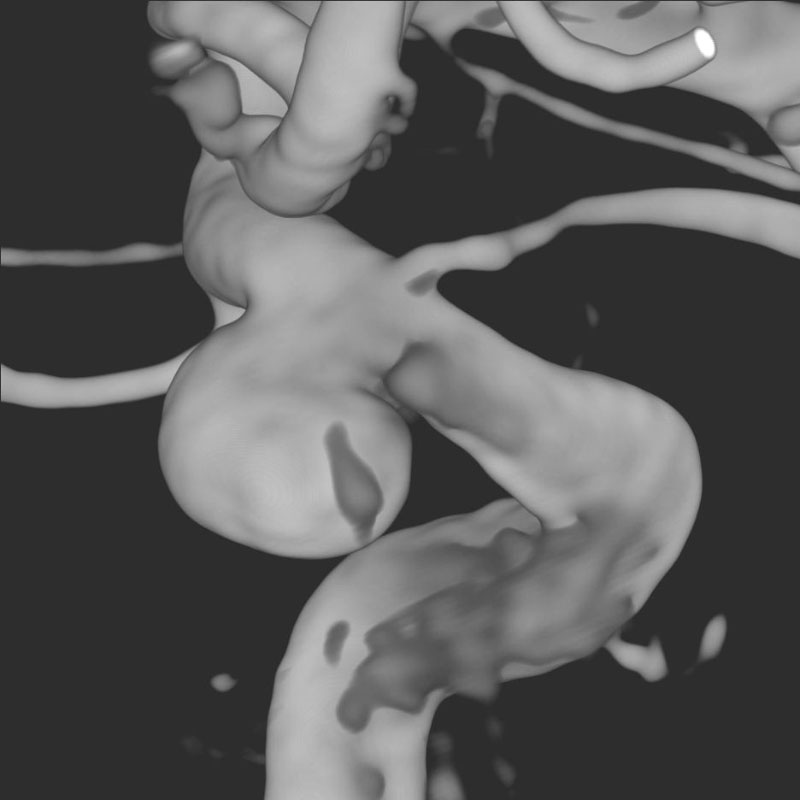

脳動静脈奇形

血管塞栓術

松田/濵田/元永